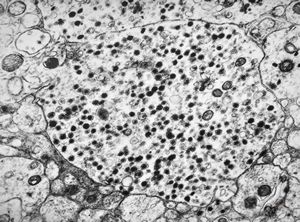

M,40y. | granular cell tumor

F,30y. | granular cell tumor